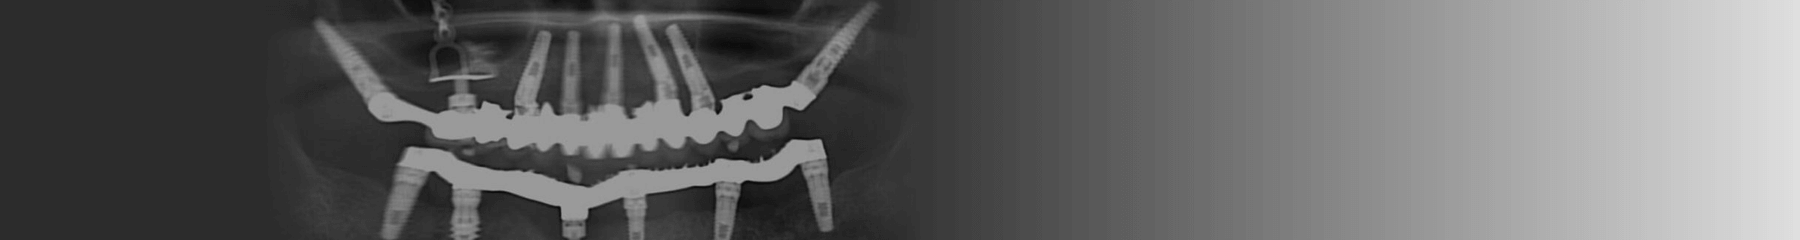

כיום, לעומת זאת, הגישה במרפאות המובילות היא להתאים שתלים דנטליים ייחודיים למצבים כאלו. כך למשל פותחו שתלים זיגומטיים שהם שתלים דנטליים ארוכים יותר המאפשרים עיגון של מערכת השיניים החדשה ישירות לעצם הזיגומה (עצם הלחי). בצורה זו ניתן להעניק למטופלים פתרון יצירתי שאינו דורש לבצע אצלם טיפולים מקדימים מורכבים וכואבים כדי "להכין את השטח" לקראת השתלת שיניים עתידית.

אחת הטכנולוגיות המתקדמות האלו היא טכנולוגיית CAD CAM, קיצור של computer-aided design and computer-aided manufacturing. טכנולוגיית CAD CAM זו לוקחת את הדמיות תלת הממד שבוצעו למטופל או המטופלת בעזרת מכשיר ה-CT, ומאפשרת לרופא השיניים לתכנן את מיקומי השתלים הדנטליים בפה ולעצב את מבנה הגשר והכתרים שיותקנו בהמשך. בדרך זו יכול רופא השיניים לקחת בחשבון את קו החיוך הטבעי של המטופל או המטופלת ולתכנן את מיקום השתלים הדנטליים לנקודות מדויקות שבהן יש עובי מקסימלי לעצמות הלסת.

אבל כאן לא מסתיים התהליך. כיום נעזרות המרפאות המובילות במדפסות תלת ממד שמאפשרות להן בקלות ובמהירות להפוך את התכנון המוקדם שנעשה בעזרת טכנולוגית CAD CAM למציאות ומאפשרות לרופא השיניים לייצר במעבדת השיניים תוך שעה מבנה מדויק של גשר וכתרים.